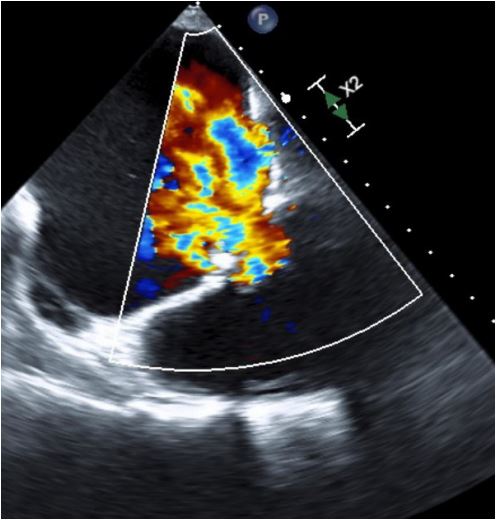

Echocardiogram (Figures 1,2) and MRI (Figure 3) showed severe dilation of the right atrium, severe tricuspid regurgitation, decreased ventricular systolic dysfunction, and dilated right ventricle. Based on his echocardiogram & MRI, it was determined that he would benefit from a tricuspid valve replacement. Preoperative type and cross was positive for cold agglutinin and needed appropriately matched blood.

Figure 2: Pre Op TEE with color showing severe Tricuspid Regurgitation (TR).